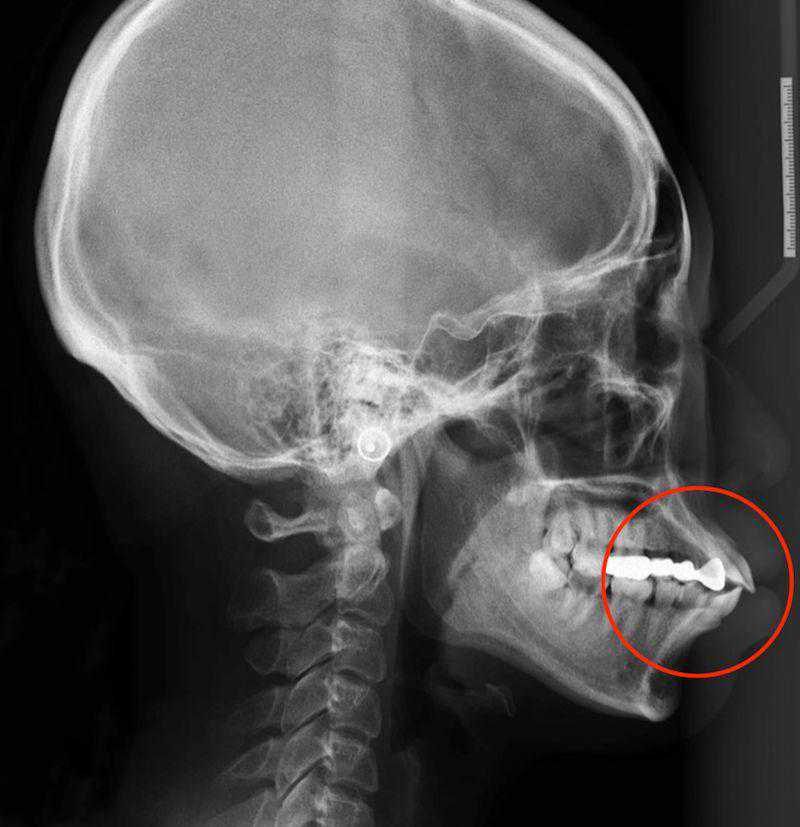

这张片子就是牙性骨性混合存在的,因为骨性程度严重,只能通过正畸+正颌手术来解决。